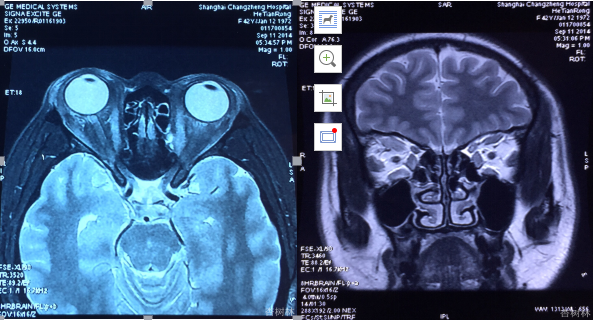

眼眶MRI

双眼眼外肌增粗。